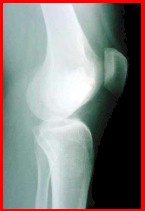

CONDROBLASTOMA

Es de la segunda década. ES EPIFISARIO NETO! Afecta los huesos largos. Son AGRESIVOS!. Muy raro.Tienden a recidivar. Muy raro dan metástasis pulmonares.(Con histología normal). Dan reacción esclerosa. Localmente se comportan como malignos.

Se resecan de abajo hacia arriba. No se abre. Se hace curetaje por hueco, injerto óseo y cemento óseo, ya que es citolítico.

Altamente recidivantes. A veces hay que hacer resecciones oncológicas.. Puede verse en trocánter mayor (siempre hay esclerosis perilesional)

Figura 8: condroblastoma